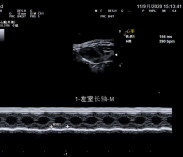

心脏解剖 M 型(CMM):

M 型取样线可 360 度任意旋转,并可同时设定 3 条自由角度取样线。同时显示 同一时相 3 条线上组织 M 型信息,实现在同一个心动周期中,在同一时相对不同的 心肌节段、瓣膜进行对比观察和测量分析。可应用于心脏和腹部探头(心脏功能评估)。

小鼠左室长轴